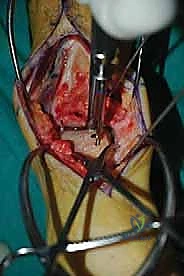

الغوص العميق في جراحة الطعم الخيفي الهيكلي (Structural Allograft Reconstruction)

يهدف هذا الإجراء العبقري إلى استبدال الغضروف والعظم التالفين والميتين بنسيج سليم تماماً مأخوذ من متبرع متوفى (طعم خيفي - Allograft). هذا الطعم يتم تعقيمه وحفظه في بنوك الأنسجة العالمية وفقاً لأعلى المعايير الطبية الصارمة لضمان خلوه من أي أمراض معدية والحفاظ على حيوية الخلايا الغضروفية.